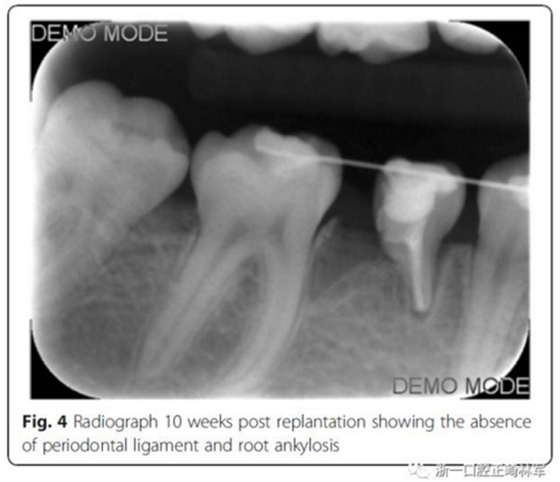

10周后,根據(jù)臨床和影像,形成乳磨牙牙槽粘連,移除牙弓夾板。下一步,在右下第一磨牙上粘接帶環(huán),在第二乳磨牙和下頜第一前磨牙上粘接托槽,在恒磨牙和乳磨牙之間安裝T型曲前移第一恒磨牙。T型曲共激活9次。